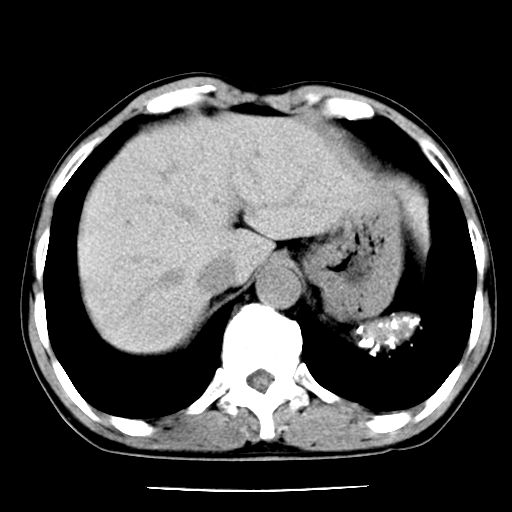

男,59岁,“结核性胸膜炎”30余年,胸部经常疼痛,多次x检查提示“肺部”炎症。腹部疼痛5日,b超提示:“肝内短管结石,余显示不清,建议进一步检查。”

两肺结核并右侧胸腔积液;脾脏、腹腔及腹膜后淋巴结结核[陈旧性];肝内胆管结石

胸部腹部都是结核(双肺。纵隔淋巴结,肝脏,脾脏,肠系膜)

两肺结核并右侧胸腔积液;脾脏、腹腔及腹膜后淋巴结结核[陈旧性];肝内胆管结石。直肠息肉?